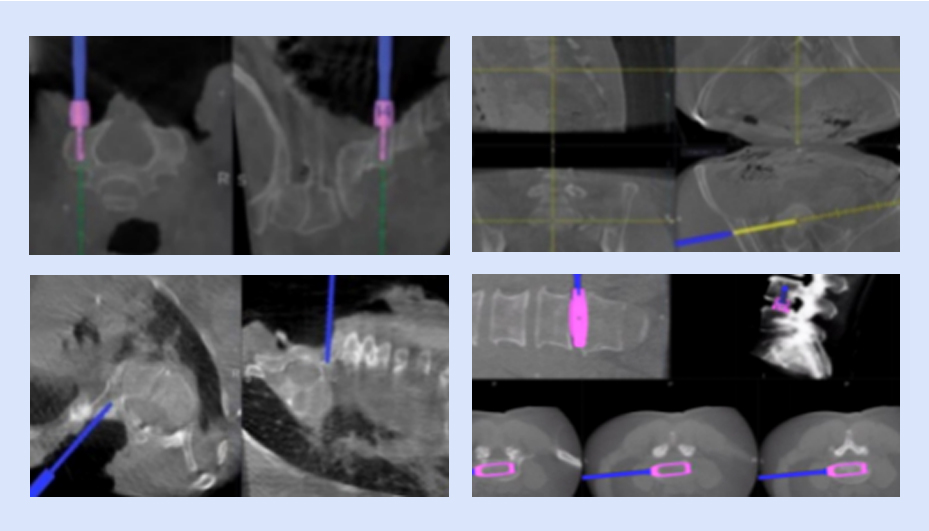

可視化置釘

確保導航設備正常運行,檢查定位系統、手術器械、置釘系統等是否完好,以及設備是否處于最佳工作狀態

可視化椎間融合

具備全套導航專用椎間融合工具,實現從椎間隙定位、放置通道、椎間處理、試模、放置融合器的全程可視化,提高手術效率,做到精準融合。